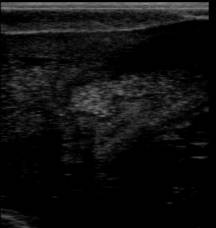

При ультразвуковом исследовании животных с

клинической картиной подострого эндометрита (желтовато-белые хлопья в мутной

слизи, при ректальном исследовании матка располагалась позади лонного сращения,

ее тонус снижен, рога опущены в брюшную полость) было выявлено утолщение

эндометрия, четкое разграничение эндометрия и миометрия. В полости матки

отмечается наличие неоднородного гиперэхогенного содержимого, что говорит о

скоплении гнойного экссудата густой консистенции (рис. 4).

Рис. 4. Ультразвуковая картина

при подостром эндометрите: 1 – эндометрий; 2 – миометрий; 3– полость матки с

жидкостью (стрелками показан сосудистый слой)